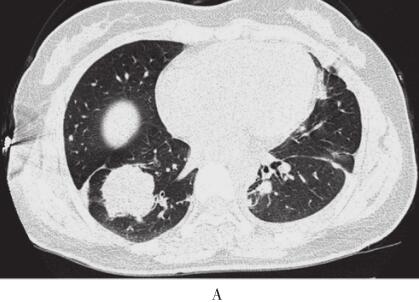

出院后定期随访,2013年7月患者出现间断左下胸痛,咳嗽时加重,余无不适。体检未见异常。复查胸部增强CT右下肺病灶较前稍增大,左下肺病灶较前减小(图2)。为排除恶性肿瘤,第3次行CT引导下经皮右肺肿块穿刺,病理检查示肺纤维化、玻璃样变及黏液变(机化),有少量炎性细胞浸润,未见肿瘤细胞。PAS染色及刚果红染色均阴性,确诊ELP。半年后患者胸痛症状有所好转,影像学同前,该病例在继续随访中。

图2 2013年7月3日肺部CT

与之前对比,右肺肿块较前稍增大,左下肺病灶较前减小